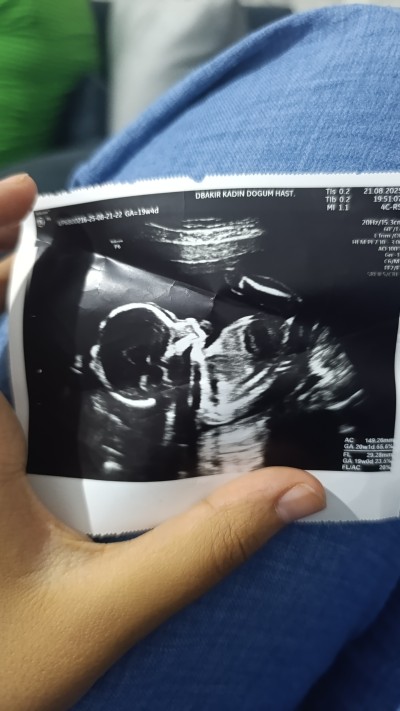

Bı bakarmisiniz kızlar

image

Gebelik haftası 20+1

Bebek Iyi  görünüyor eli ayağı oluşmuş ve sen şuan tekmelerini hisediyomusun

Hisediyom da cinsiyet için paylaşmiştim hep hata veriyor bide böyle atayım dedim :)